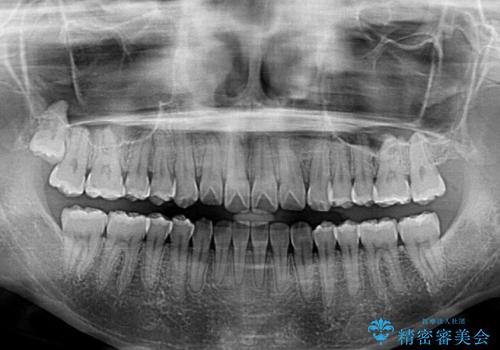

オープンバイトのインビザラインを用いた再矯正

- 矯正治療の後戻りを気にして来院された患者様です。

オープンバイト(前歯の開咬)と下顎骨の偏位による不正咬合が認められました。

骨格の偏位による不正咬合は改善しきれないことを理解いただいた上で、インビザラインにて矯正治療を行うこととしました。

オープンバイトは後戻りを起こしやすいため、極力そのリスクを軽減するため、奥歯を圧下させるように治療を進めていきました。

下顎骨の偏位が顕著であったため、上下の正中を合わせることはできませんでしたが、患者様には大変満足していただきました。